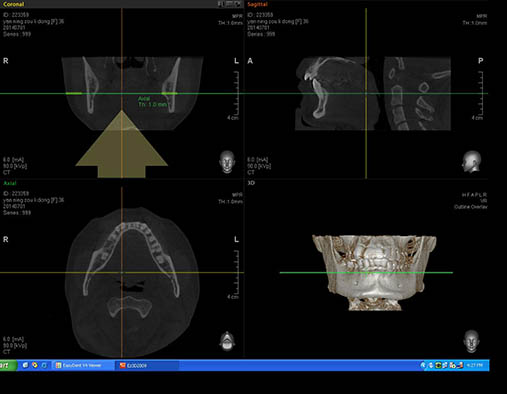

放射科成立于2001年6月,目前有数字牙片机2台、数字全景机1台,口腔CT机1台,设备均为数字成像,并由5名专业的全职放射技师操作,确保了影像的效果和质量。

目前我院放射科拍摄的数字X线片包括:牙片、曲面断层、头颅正侧位、手腕骨片、口腔CT片(CBCT)。另外我院放射科严格执行每人一副手套、一次性消毒探头套的消毒管理制度,杜绝交叉感染。同时,拍照时给患者穿戴铅围脖,使患者非受照部位的剂量降到最低。